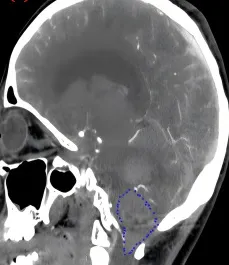

一名21岁女性突然出现头痛,伴随恶心和严重的弹射性呕吐,持续了整整12个小时。症状不断加重,入院30分钟后即陷入深度昏迷。影像检查发现,从小脑、延髓延伸至脊髓,一个巨大的血管母细胞瘤已经破裂出血。血管母细胞瘤虽是良性肿瘤,但血供极为丰富,如果能及时进行手术切除,预后通常良好。遗憾的是,这名患者在确诊的那一刻已经失去了手术机会。生命禁区的肿瘤,从不容许半点疏忽。

与上述病例形成对比的,是华裔德国精英高管W先生的故事。虽然都是延髓血管母细胞瘤,但W先生的结局完全不同。W先生因持续加重的身体麻木就医,检查发现延髓背侧存在血管母细胞瘤,好在没有出现更严重的急性事件。血管母细胞瘤的手术治疗效果通常不错,偏偏这种肿瘤血供量极大,手术难度不小。尤其是长在延髓上的病变,术中稍有不慎就可能影响患者的呼吸、心跳和血压。W先生和家人决定,既然要治,就一定要找最好的医生。

通过INC国际神经外科,W先生联系上了巴教授。巴教授的评估是:如果用1到10分来评价这台手术的难度,他给它打5到6分。言下之意是,有些医生认为这类手术风险极高,甚至根本无法开展,但对他来说这是常规手术。术前规划、麻醉方案、手术体位、术中操作的每一步精准执行、术后管理——任何一环出现疏漏,都可能带来无法挽回的后果。最终,W先生选择在北京天坛医院由巴教授主刀手术。